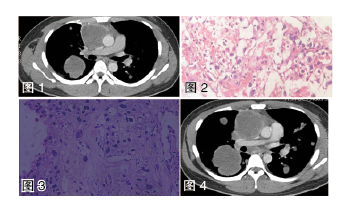

辅助检查  入院后血、尿、大便常规、肝肾功能无明显异常;血沉:42 mm/h;C反应蛋白15.60 mg/dl;肿瘤相关抗原:人绒毛膜促性腺激素(β-HCG)29.1 MIU/ML,癌抗原125(CA125)70.12 KU/L,余项正常;免疫球蛋白、抗核抗体谱、血管炎抗体、抗ENA抗体、类风湿因子、结核感染T细胞斑点实验、G试验、GM试验均阴性。肺部CT平扫+增强(8月12日)示(图1):前上纵隔占位、双肺多发结节及肿块。8月22日病理结果(图2):镜下见坏死组织中少量核增大的细胞,可疑恶性肿瘤,建议重新活检。此时完善尿妊娠试验阳性,性激素检查提示异常,并再次进行生殖系统体格检查,发现患者双侧乳房轻度肿大,左侧睾丸萎缩。

8月26日病检结果(图3)示:恶性肿瘤,肿瘤细胞体积大,大部分胞浆丰富透明,胞核圆形,可见明显核仁及病理性核分裂,个别细胞呈合体状,肿瘤细胞与血管关系密切。免疫组化:HCG(小区+),Ki67(约60%~70%+),CK-Pan(+),P40(灶性+),AFP、PLAP、CD30、CD117、Vimentin、TTF-1均(-)。结合临床、影像及免疫组化考虑绒癌。复查肺部CT平扫+增强(9月2日)示(图4):纵隔占位、双肺多发结节及肿块病变考虑生殖细胞瘤并多发肺内转移,病变较前明显进展。乳腺、腋窝、腘窝、阴囊、腹股沟、颈部彩超(9月1日)示:双侧颈部、左侧锁骨上窝、右侧腹股沟区多个淋巴结声像,左侧附睾头囊肿(睾丸无病灶)。

诊断  纵隔原发性绒毛膜上皮癌(肺内多发转移 Ⅲb期 高危组)。